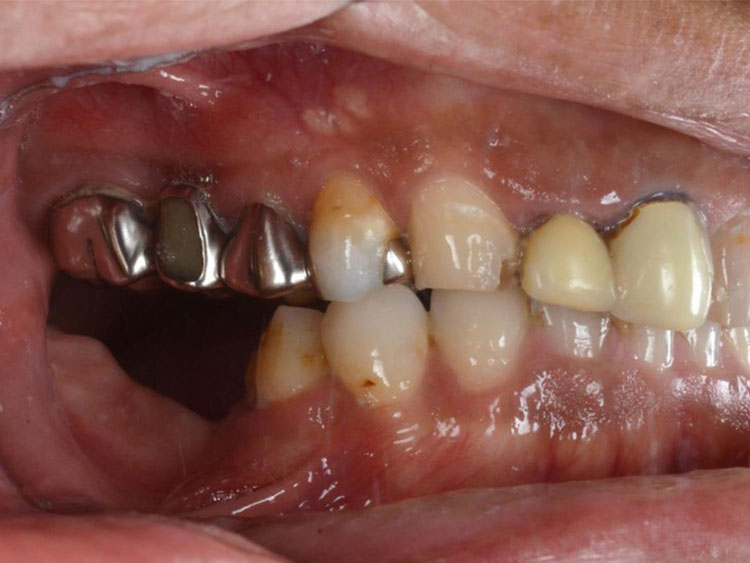

インプラント症例 Case2

Treatment cases

Before

After